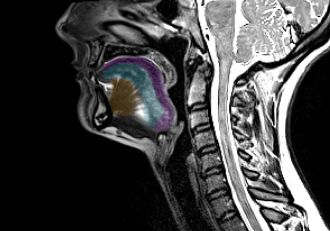

A study conducted at the Paris Brain Institute in 2023, published in the journal Neurobiology of Disease, identified a phenomenon termed the “death wave.” This research revealed that when the brain is deprived of oxygen, as occurs during cardiac arrest, it does not immediately fall silent. Instead, there is a final surge of activity characterized by gamma and beta waves, typically associated with conscious perception, memory recall, and complex thought. It is as if consciousness makes a last vibrant appearance.

Following this initial burst, a massive wave of electrical depolarization sweeps across the cerebral cortex, silencing neurons in its path. This event represents the true “death wave.” Remarkably, if oxygenation is restored in time, this wave can be reversed by a “resuscitation wave,” potentially returning the brain to a functional state.